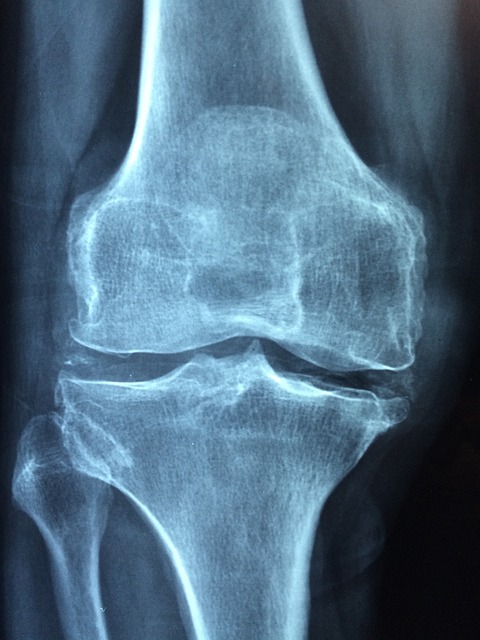

관절염을 진단하기 위해 의료 전문가들은 증상을 평가하고 관절을 검사하며 근본적인 원인을 식별하는 다양한 방법을 사용한다. 이 섹션에서는 관절염에 사용되는 몇 가지 일반적인 진단 접근법을 탐구할 것이다. 신체 검사는 필수적인 단계이며, 이 과정에서 의료 제공자는 관절의 부드러움, 붓기 및 운동 범위를 평가합니다. 그들은 또한 개인의 병력을 조사하고 관절 손상을 평가하고 다른 조건을 배제하기 위해 엑스레이, MRI 또는 초음파와 같은 영상 검사를 수행할 수 있다. 염증 마커와 특정 항체를 포함한 혈액 검사는 류마티스 관절염과 같은 특정 유형의 관절염을 식별하는 데 도움을 줄 수 있다. 경우에 따라 관절액 분석 또는 생검이 최종 진단을 위해 필요할 수 있습니다. 적절한 치료를 시작하고 관절염을 효과적으로 관리하기 위해서는 시기적절하고 정확한 진단이 중요하다.